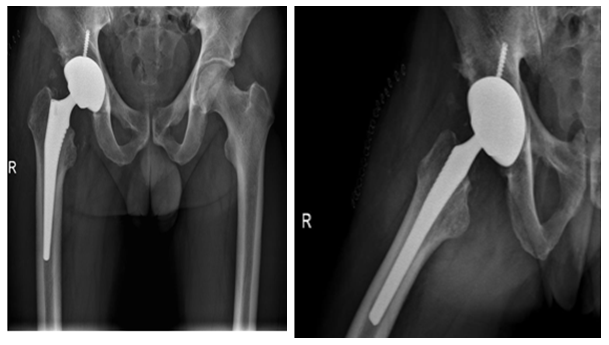

Two stage treatments consisted in an initial surgery through a posterior approach, debridement of inflammatory tissues, neck osteotomy and acetabular reaming adding a temporal non-articulated antibiotic impregnated cement spacer for the resected femoral head. 6 weeks after surgery when intravenous antibiotic treatment was completed and laboratory inflammatory parameters were controlled, a second stage surgery was planified: Conversion to a hybrid arthroplasty for the first case and a non cemented total hip arthroplasty for the second case (Figure 1) (Figure 2).

Figure 1: 60 year old diabetic male patient. A and B Plain X rays showing the narrowing of the hip joint, consequent to a psoas absess. C, D are MRI images showing the acetabular edema and sinovytis associated to psoas edema. E and F postoperative arthroplasty x-ray. Differed anatomy showed chronic inflammation compatible with osteomielitis but no germs were isolated in the cultures. Harris Hip score was 94 at 2 year follow up, infection markers controlled and no complications were reported.